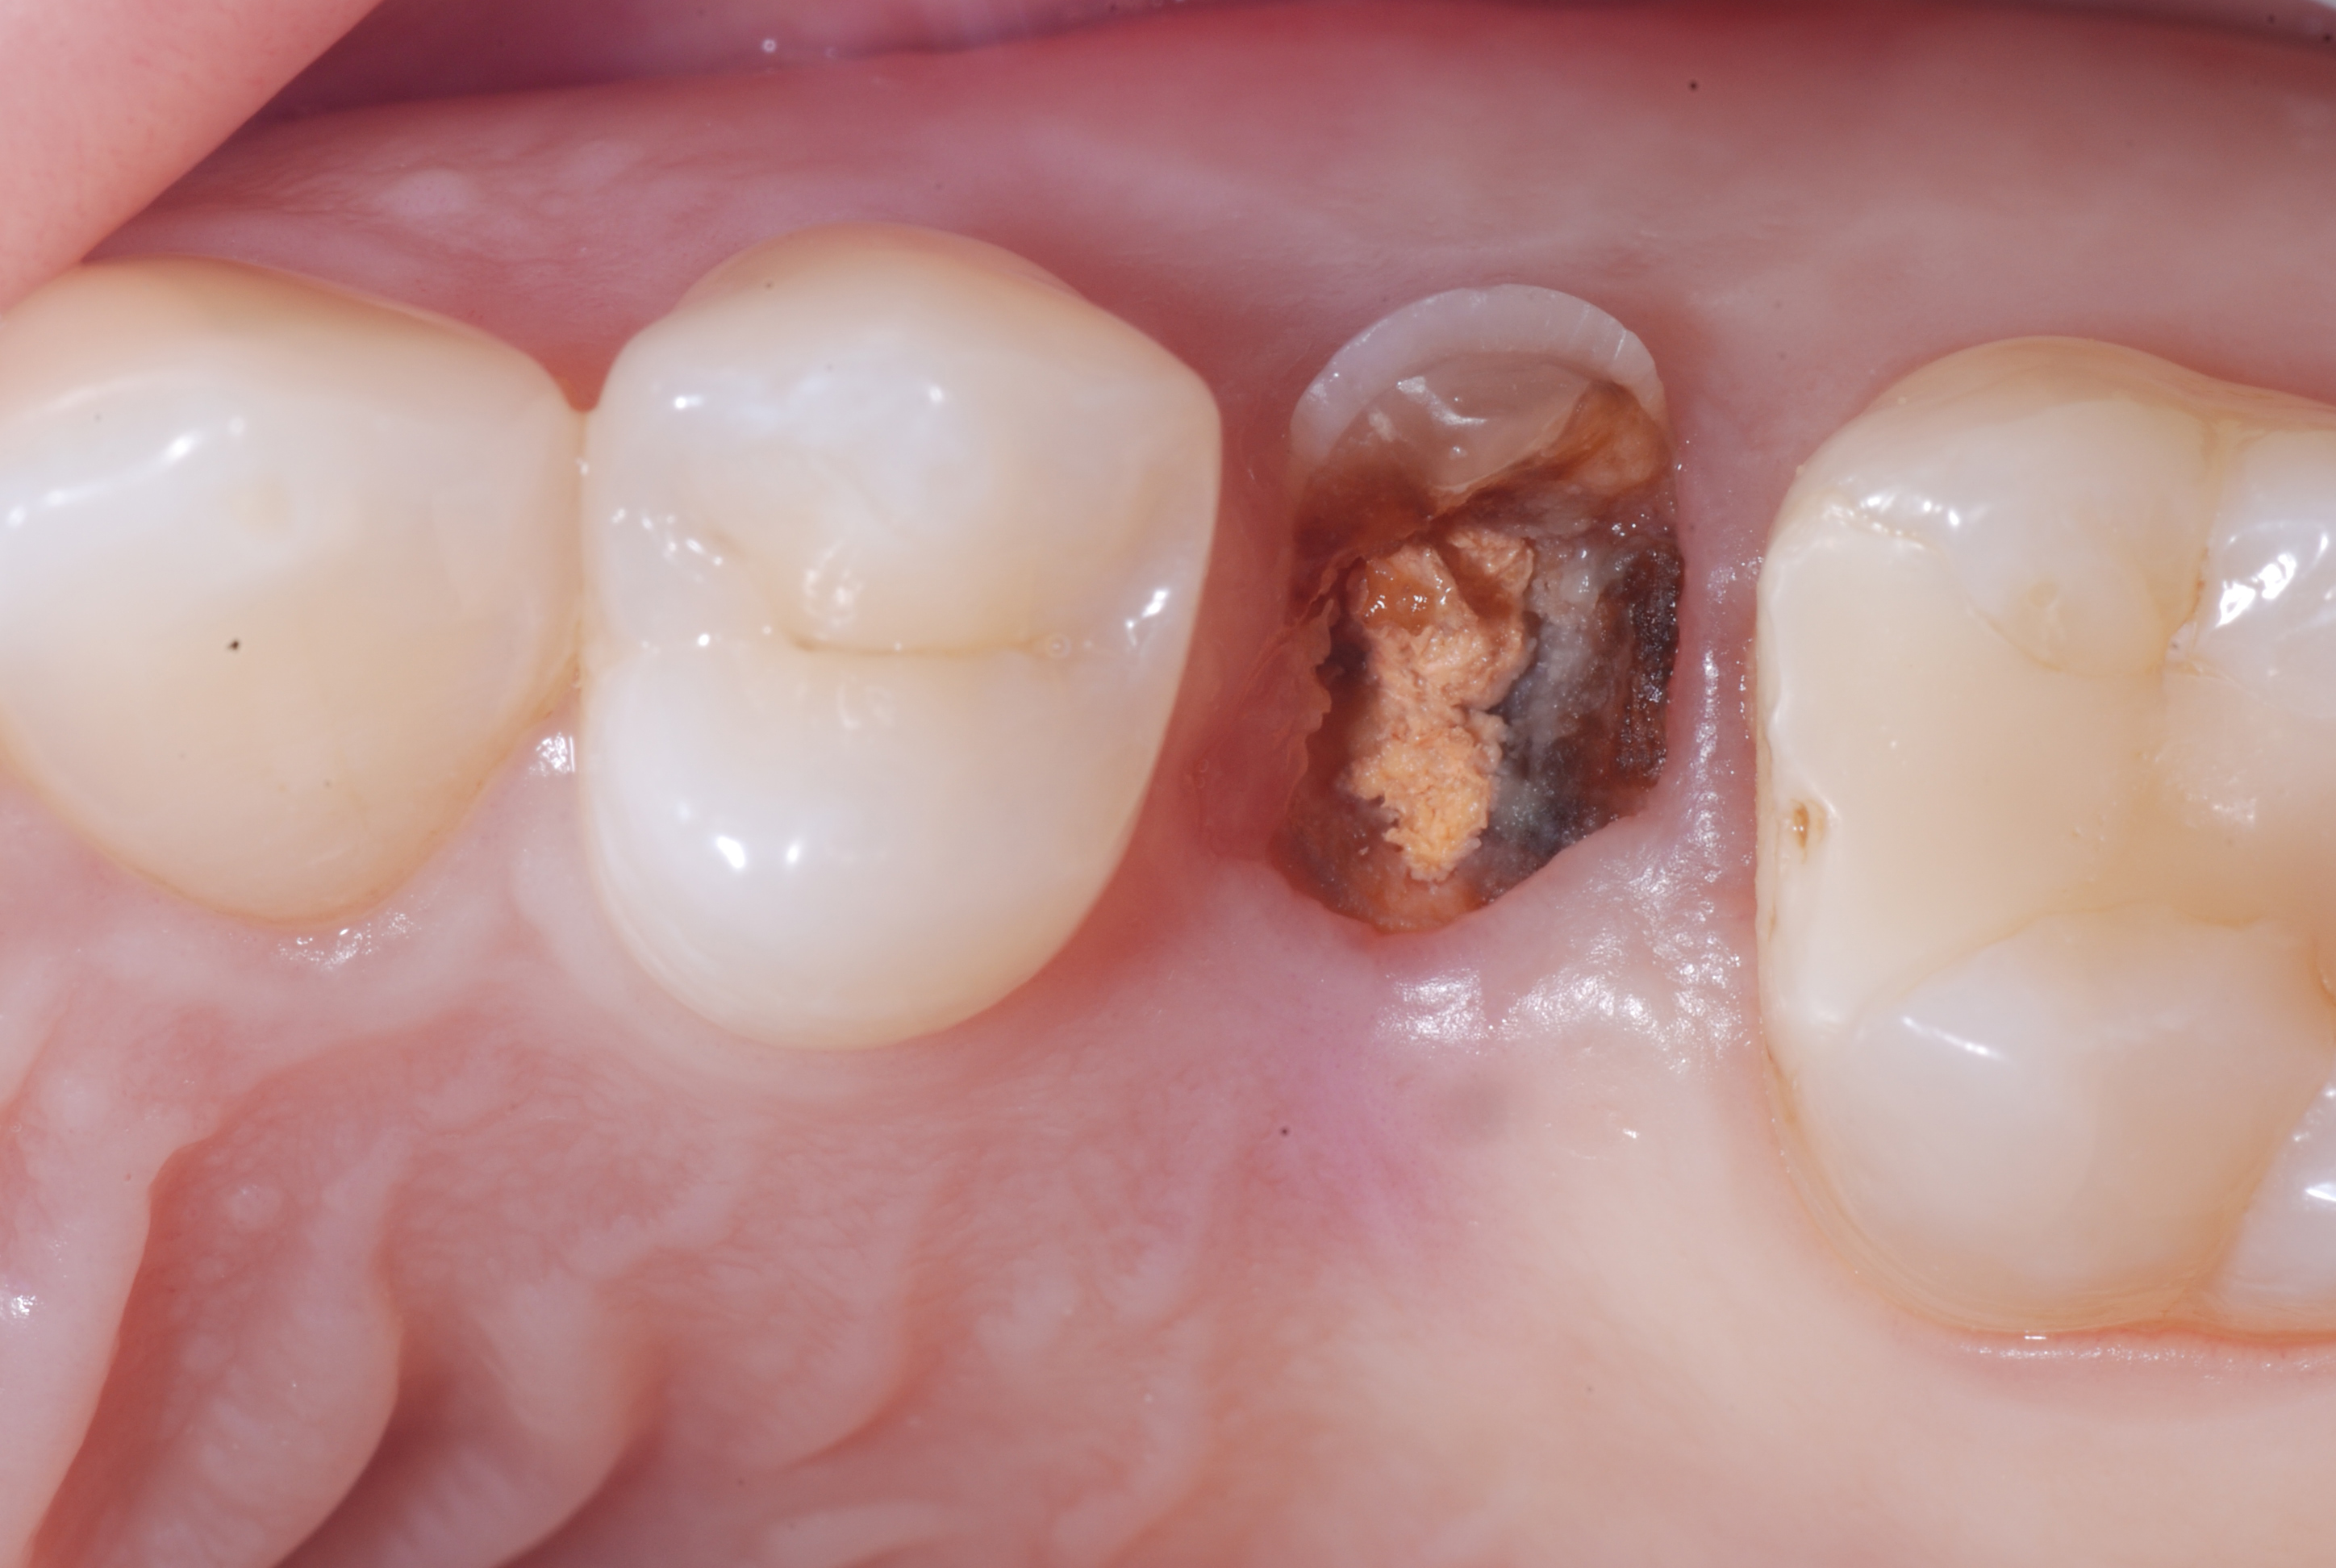

Figure 1. Bite Wing X-ray and Apical X-ray of tooth 25 completely compromised by the carious process.Figure 2. Clinical image of tooth 25 totally destroyed at the coronal level.